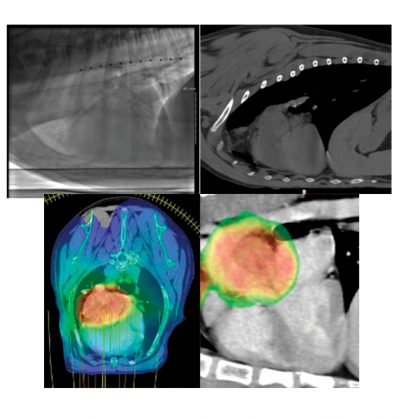

A month later, once Lola recovered from surgery, a CT scan and fluoroscopy of her chest were performed to evaluate the extent of the tumor. This was done to make sure the tumor had not spread to other organs, to facilitate a plan for radiation therapy, and determine how much the heart moved in the chest while it was beating. Fortunately, there was no evidence of cancer in other organs and there was very little fluid buildup in her chest cavity.

Due to many factors, Lola’s veterinary healthcare team felt that stereotactic radiation therapy (SRT) was the best choice of treatment for her. This protocol involves 1 treatment per day for 3 consecutive days, under general anesthesia; high doses of radiation are delivered to the tumor while using advanced technology to protect the nearby tissues. Her prescription was 10 Gray times 3 treatments, for a total of 30 Gray (the unit of radiation therapy prescriptions; 1 Gray = 1 joule per kilogram of tissue).

Lola was brought to MSU for SRT treatment from Tuesday, May 26 through Thursday, May 28. Each visit, she was placed under general anesthesia and positioned for radiation therapy. A cone-beam CT scan was performed to verify her tumor and make certain all her normal organs were in the correct position before treatment. A technique known as volumetric modulated arc therapy (VMAT) was used. She recovered uneventfully each day.